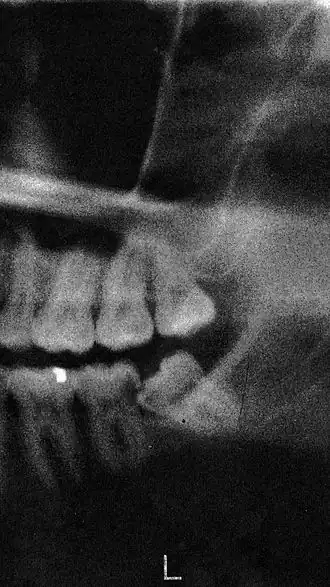

Een verstandskies die horizontaal geïmpacteerd was

Wanneer een verstandskies voor problemen zorgt, kan de tandarts de verstandskies verwijderen. Wanneer hij het verwijderen van een verstandskies als moeilijk beschouwt, zal hij de patiënt vaak doorverwijzen naar een kaakchirurg. Vaak zal van tevoren een röntgenfoto van de verstandskies gemaakt moeten worden om de wortelstructuur van de verstandskies te kunnen zien. Wanneer de kaakchirurg het besluit neemt, dan wordt de kies onder plaatselijke verdoving getrokken. In enkele gevallen wordt de verstandskies in twee of drie delen verwijderd. Wanneer de patiënt angst voor dit soort behandelingen heeft, dan kan diegene kiezen om de verstandskiezen onder sedatie te laten trekken. Dit gebeurt vaak poliklinisch. Een alternatief is de verstandskiezen onder narcose laten trekken, dit vereist wel een dagbehandeling of een opname in het ziekenhuis. Deze ingreep duurt maximaal een uur.